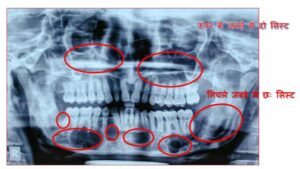

बिलासपुर-[जनहित न्यूज] छत्तीसगढ़ आयुर्विज्ञान संस्थान (सिम्स) के दन्त चिकित्सा विभाग द्वारा दुर्लभ बीमारी गोर्लिन गोल्त्ज़ सिंड्रोम से ग्रसित व्यक्ति की बीमारी का डायग्नोसिस कर सफल ऑपरेशन किया गया। कोरबा जिले के 35 वर्षीय मरीज रमेश यादव पिछले एक से डेढ़ साल से अलग अलग जगह इलाज करवाते रहे किन्तु फिर भी उसे समुचित उपचार नहीं मिला, क्योंकि कोई सही डाइग्नोसिस ही नहीं कर पाया। उल्लेखनीय है कि यह बीमारी अत्यंत दुर्लभ है और इसका डाइग्नोसिस करना भी उतना ही कठिन है। मरीज रमेश यादव सिम्स के दन्त चिकित्सा विभाग आने के बाद सबसे पहले मरीज का हिस्ट्री लिया गया, फिर फिजिकल एग्जामिनेशन किया गया। कुछ एक्स-रे लिया गया, बाईओप्सी की गई, इससे सम्बंधित ऑनलाइन डाटा सर्च किया गया। तत्पश्चात इस बिमारी को डाइग्नोस किया गया।

गोर्लिन गोल्त्ज़ सिंड्रोम बीमारी जो कि बहुत ही दुर्लभ है। भारतीय मरीजों में 1960 से लेकर अब तक 48 मरीजों में गोर्लिन गोल्त्ज सिंड्रोम बीमारी होने के लक्षण मिले। जिनमे से केवल 38 मरीज ही गोर्लिन गोल्त्ज सिंड्रोम के कन्फर्म हुए हैं। जिनका इलाज मुंबई, दिल्ली, बंगलौर जैसे शहरों में हुआ। गोर्लिन गोल्त्ज़ सिंड्रोम को डाइग्नोस करने के लिए अपनाई जाने वाली विधि में या तो 2 मेजर एवं एक माइनर क्राइटेरिया अथवा एक मेजर एवं 2 माइनर क्राइटेरिया का होना बहुत ही आवश्यक है। हमारे मरीज में तीन तरह के मेजर क्राइटेरिया पाए गए।

सिम्स के दन्त चिकित्सा विभाग द्वारा मरीज के दोनों जबड़े से मल्टीपल जॉ सिस्ट को निकाला गया तथा कॉरनॉय शोलयूशन से डिसइंफेक्ट किया गया। अवगत हो कि ऐसे जॉ सिस्ट के रेक्यूरेंश रेट काफी हाई होते जो कि 60 प्रतिशत तक होते हैं। ऑपरेशन के बाद मरीज एक हफ्ता भर्ती रखकर इलाज किया गया।